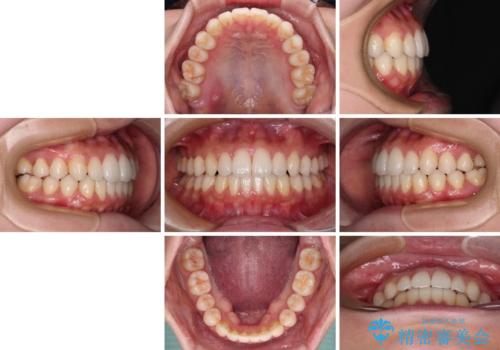

インビザラインで口を閉じやすく

- 下唇に上の前歯が当たることを気にして来院された患者様です。

上顎の親知らずを抜去し、歯列全体を後方に移動させるとともに、IPR(歯と歯の間を削る)を行うことで口元の閉じにくさを改善していくこととしました。

咬合力が強く、マウスピースを介した咬み込みが顕著であったため、奥歯の咬みにくさやIPRのスペースが改善しにくく、治療期間が思った以上にかかってしまいました。